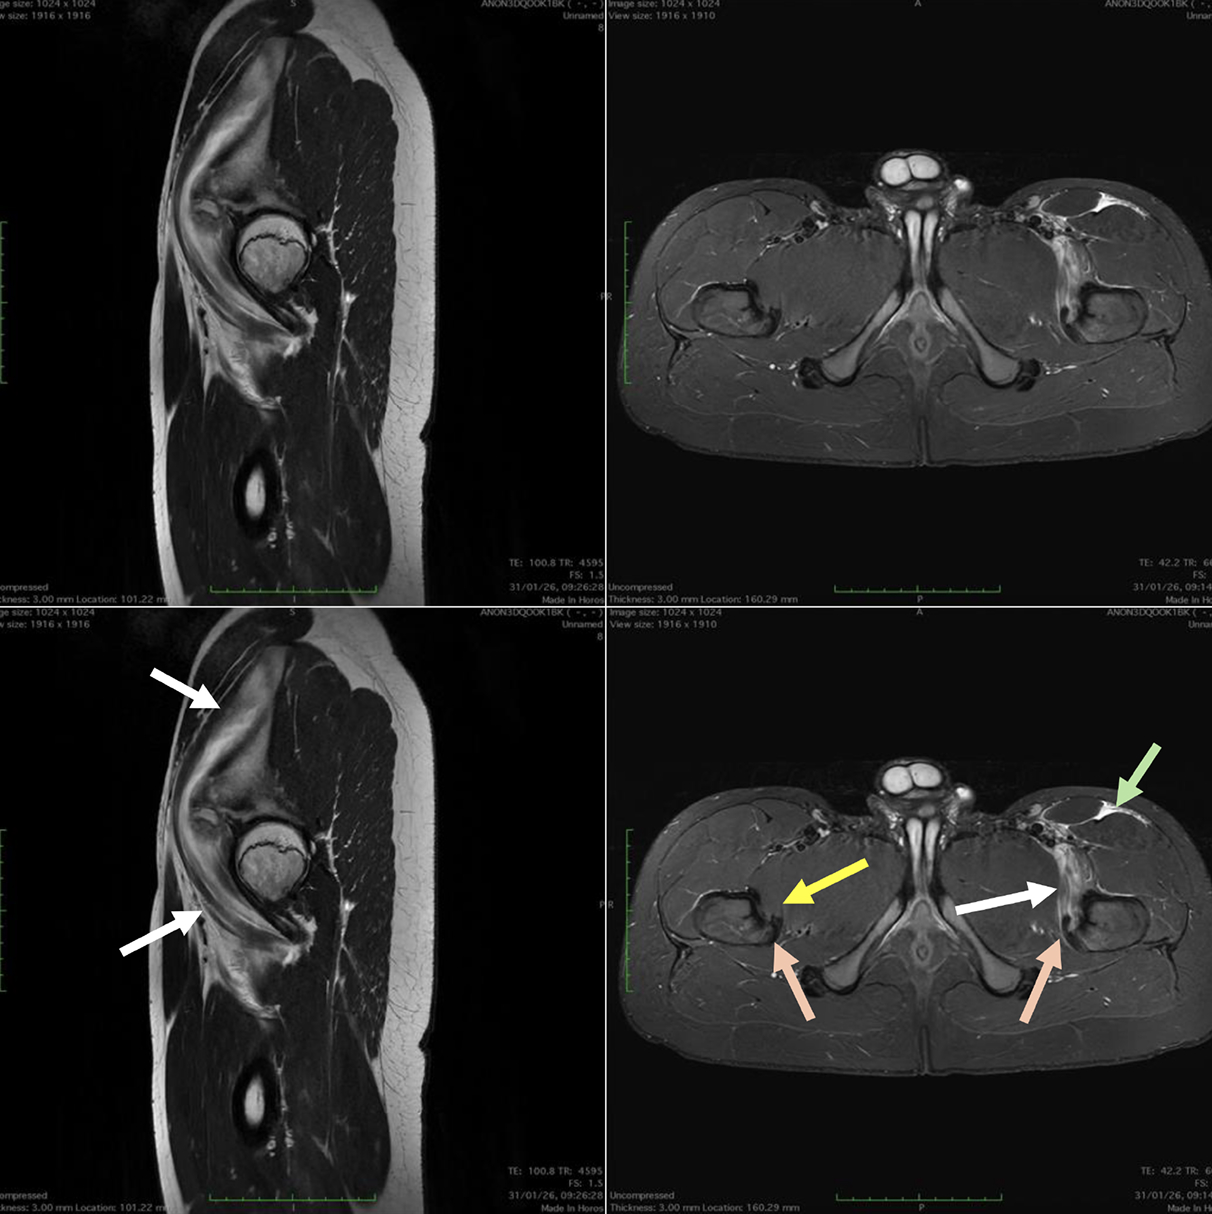

Casi clinici

Scopri come le tecnologie di imaging più innovative di GE HealthCare hanno giocato un ruolo chiave nella diagnosi di condizioni cardiache complesse.